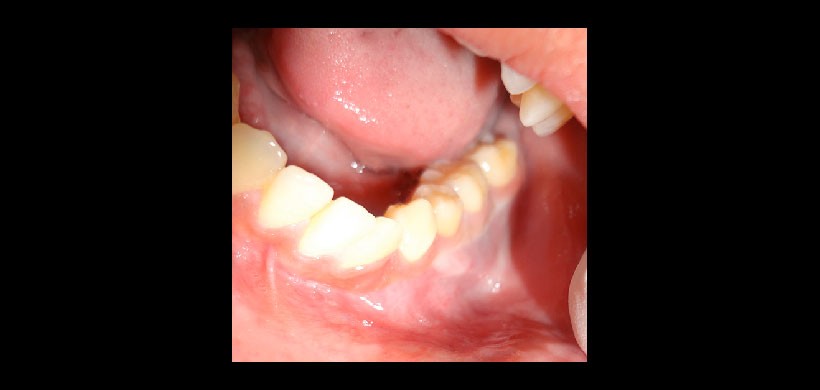

Fig 2. Examen clínico intraoral que evidencia leve aumento de volumen de la tabla ósea vestibular, de consistencia firme.